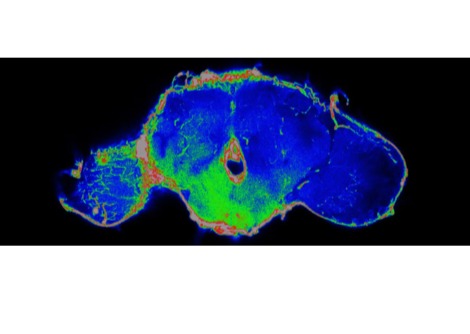

في دراستهم، فحص الباحثون السجلات الطبية لأكثر من 32,000 مريض بأمراض جلدية، بما في ذلك استخدامهم لأجهزة تسمير البشرة، وتاريخ إصابتهم بحروق الشمس، والتاريخ العائلي للإصابة بسرطان الجلد. كما حصلوا على عينات جلدية من 26 متبرعاً، وقاموا بتحليل تسلسل 182 خلية.

أظهرت النتائج أن مستخدمي أجهزة تسمير البشرة من الشباب لديهم طفرات جلدية أكثر من الأشخاص الذين يكبرونهم بضعف أعمارهم، وخاصة في أسفل الظهر، وهي منطقة لا تتعرض لأضرار كبيرة من أشعة الشمس، ولكنها تتعرض بشكل كبير من أجهزة تسمير البشرة.